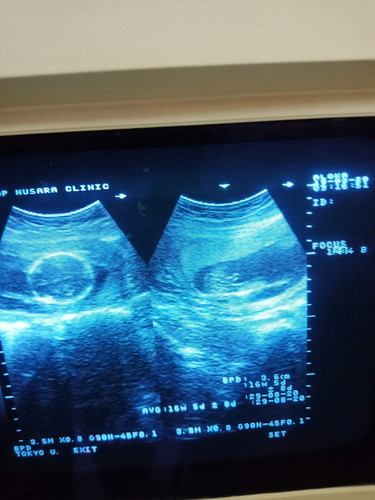

แบบนี้ผู้หญิงหรือผู้ชายค้ะ

รูปขวา ดูๆ น่าจะเด็กชายจ๊ะแม่มีจู๋จ๊ะ